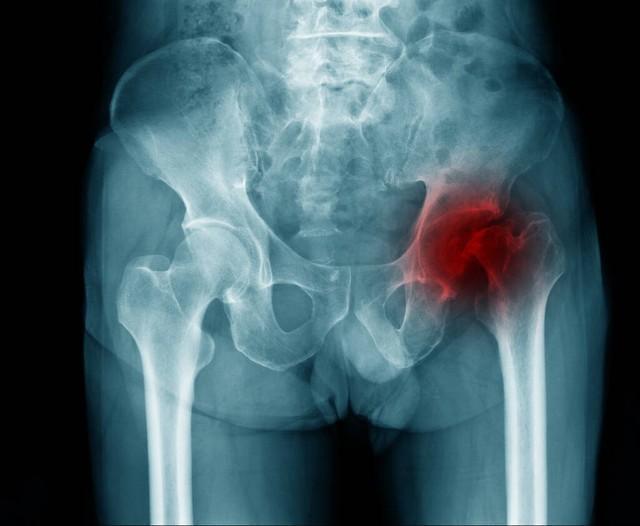

骨頭壞死是指骨組織因各種原因導致血液供應不足,從而使骨細胞死亡和骨組織破壞的過程,骨頭壞死的原因包括創傷、感染、長期應用激素、骨質疏松等,骨頭壞死后,患者可能出現疼痛、腫脹、活動受限等癥狀。